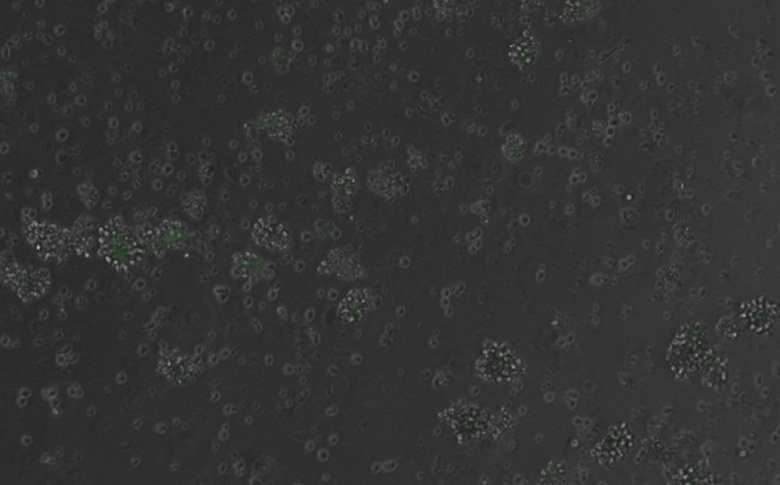

Ученые синтезировали эти фрагменты химически и с помощью вируса доставили их в клетки крови мышей. В экспериментах ДНК интегрировалась в геном клеток в случайных местах. ИИ спроектировал энхансеры, которые активировали ген, кодирующий флуоресцентный белок, чтобы ученые могли видеть, работает ли система. Результаты были точными: гены включались в нужных клетках, не затрагивая другие.